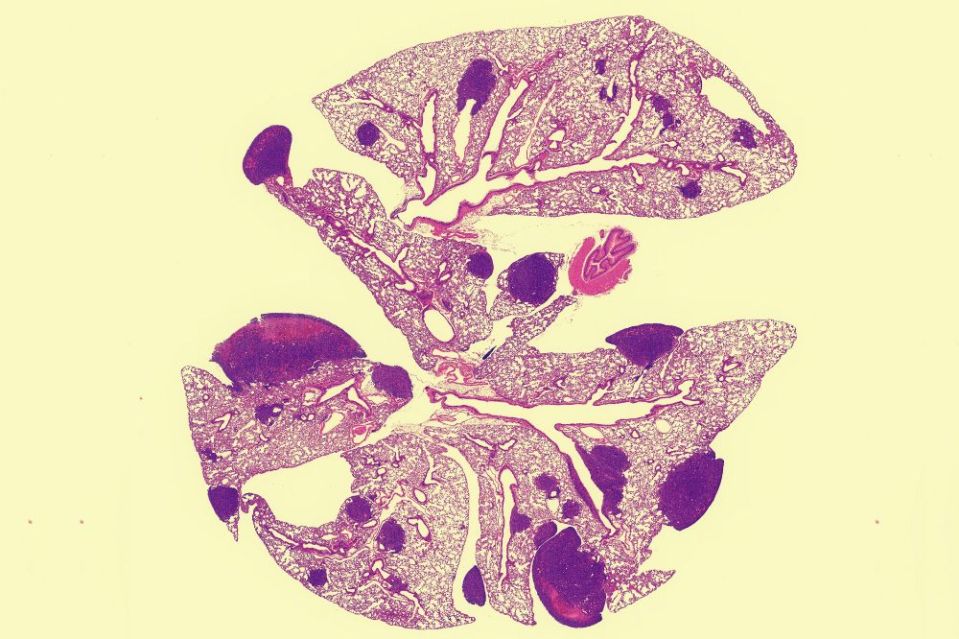

Mouse lung tissue showing PCSK9’s impact

When mice are engineered to carry a variant of the human PCSK9 gene, they experience higher rates of breast cancer metastasis, as is apparent in this image of mouse lung tissue showing PCSK9’s impact. (Credit: Tavazoie Lab, The Rockefeller University)

After the initial analysis implicated PCSK9, Mei acquired more patient data from Europe and collaborated with Swedish researchers who confirmed these findings in Scandinavian women with early-stage breast cancer. Mei also turned to the lab to explore the mechanisms underlying the effect on metastasis and to untangle this from the gene’s known role in cholesterol control. In experiments in mice whose genomes included the PCSK9 variant, breast tumors metastasized aggressively to the lungs. However, altering PCSK9 in tumors alone did not encourage metastasis. And while high cholesterol levels can promote cancer, feeding the animals high-cholesterol diets indicated that high LDL levels on their own also did not explain the increase in metastasis.